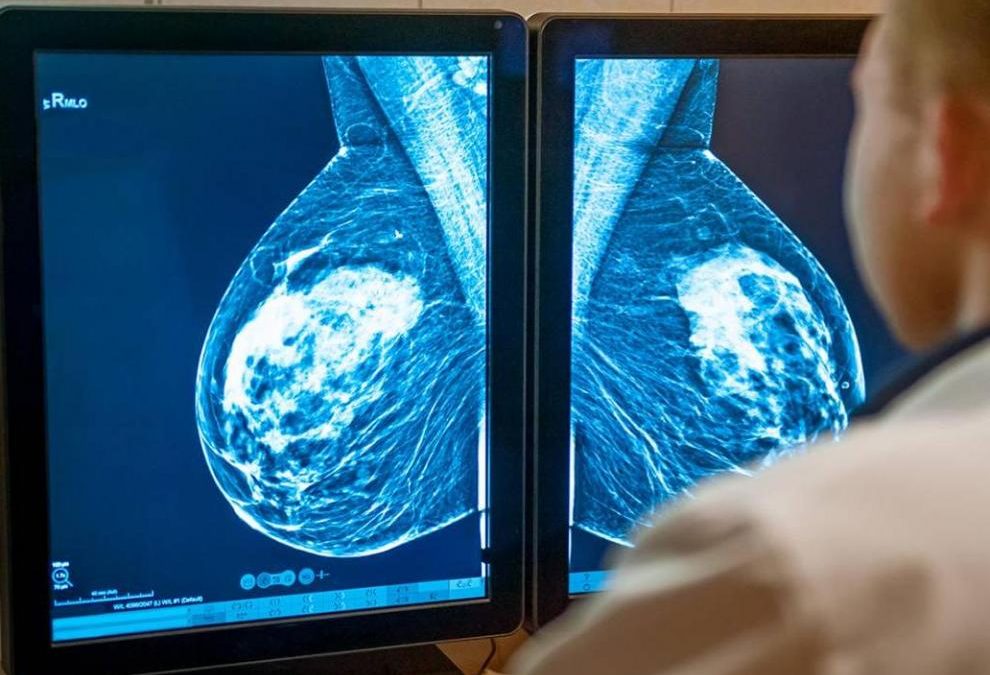

Entre los diversos subtipos de cáncer de mama, el denominado luminal es el más frecuente, pero muchas de las mujeres que lo padecen van a poder evitar el habitual tratamiento de quimioterapia.

En concreto, las pacientes postmenopáusicas con estos marcadores: receptores hormonales positivos (RH+), receptor del factor de crecimiento epidérmico 2 (HER2) negativo, tener entre 1 y 3 ganglios axilares afectados y con un resultado del denominado recurrence score (puntuación que estima el riesgo de recurrencia y la probabilidad de beneficiarse de la quimioterapia) igual o inferior a 25.

Las pacientes que cumplan esos requisitos, que representan alrededor de 5.300 nuevos casos anuales en España y actualmente son tratadas con quimioterapia más hormonoterapia, podrán prescindir de la primera y ser tratadas con igual eficacia y pronóstico solo con la segunda. Es decir, recibir solo hormonoterapia y evitar la ‘quimio’ y sus efectos adversos.